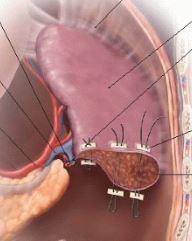

Here, we see pledgeted sutures for partial resection of the spleen, and for plication of the diaphragm.